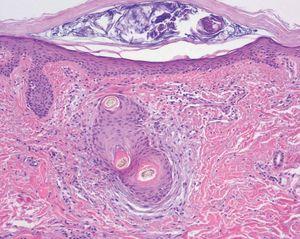

Varón de 48 años, sin antecedentes personales ni familiares de interés, que presentaba cuadro de diarrea crónica de más de un año de evolución y síndrome general, con astenia, anorexia y adelgazamiento de más de 15 kg de peso que le confería un aspecto caquético, con poliadenopatías de 2-3 cm de diámetro, elásticas y no adheridas a planos profundos en cuello, axilas y región inguinal. Posteriormente, desarrolló un cuadro de demencia subcortical, con cambios en el comportamiento, déficit de memoria, ataxia y hemiparesia IV/V derecha. En la exploración cutánea se observaron encías edematosas que sangraban con facilidad (fig. 1), lesiones purpúricas en piernas, de predominio folicular (fig. 2), así como descamación cutánea generalizada ictiosiforme (fig. 3). En las pruebas complementarias destacaban hemoglobina 9,2 g/dl; volumen corpuscular medio 100 fl; 2.500 leucocitos con fórmula normal; velocidad de sedimentación globular 55 mm y datos de malnutrición severa con prealbúmina 8 mg/dl (normal 10-40) y retinol 1,3 mg/dl (normal 3-6); vitamina B12 171 pcg/ml (normal 211-911), ácido fólico 0,5 ng/ml (normal > 1,6); niveles séricos de ácido ascórbico 7 micromol/l (normal 20-80 micromol/l); enzima conversora de angiotensina 71,3 U/l (normal 8-55); proteinograma con Ig M < 30 mg/dl; serologías hepatitis B, C, lúes y virus de la inmunodeficiencia humana, negativas; coprocultivos y parásitos en heces, negativos; bacilos ácido-alcohol resistentes en esputo y orina, negativos; Mantoux 0 mm; bioquímica y recuento celular de líquido cefalorraquídeo normal; radiografía de tórax normal; resonancia magnética nuclear cerebral con áreas extensas de desmielinización de sustancia blanca supra e infratentorial. Se realizó endoscopia del tubo digestivo con estudio anatomopatológico, observando a nivel del estómago gastritis crónica activa y la presencia de granulomas epitelioides no necrotizantes a nivel del duodeno, colon e íleon, sin observarse bacilos ácido-alcohol resistentes. La biopsia de un ganglio linfático axilar demostró una linfoadenitis granulomatosa no necrotizante. El estudio histológico de las lesiones purpúricas de las piernas mostró folículos pilosos con hiperqueratosis folicular y discreta hemorragia perifolicular (fig. 4). En la biopsia de lesiones de piel de tórax se observó una epidermis ligeramente adelgazada con hiperqueratosis de apariencia laminar sin paraqueratosis y atenuación de la capa granulosa (fig. 5). Con todos estos datos inicialmente se estableció el diagnóstico de enfermedad granulomatosa idiopática generalizada (probable sarcoidosis) y se instauró tratamiento corticoideo oral, con escasa mejoría del cuadro clínico. Posteriormente, ante la escasa respuesta al tratamiento, se revisaron todas las biopsias, y aunque no se encontraron macrófagos PAS positivos en las mismas, se enviaron muestras de biopsia duodenal, sangre y líquido cefalorraquídeo para la determinación de fragmentos genómicos de Tropheryma whippelii mediante reacción en cadena de la polimerasa (PCR) y para microscopía electrónica, que fueron positivos en las muestras duodenales. Ante estos resultados se estableció el diagnóstico de enfermedad de Whipple, forma granulomatosa pseudosarcoidótica, con malabsorción intestinal secundaria que condicionó cuadro de malnutrición extrema, escorbuto, ictiosis adquirida y anemia megaloblástica. Se instauró tratamiento con imipenem más estreptomicina durante 15 días, seguido de trimetropim-sulfametoxazol, así como complejos vitamínicos con vitamina C y vitamina B12. A las pocas semanas se produjo una completa resolución de las lesiones cutáneas y de la diarrea, así como ganancia de 10 kg de peso. En el control gastroscópico al mes del tratamiento no se observaron lesiones macro ni microscópicas. A pesar de completar el tratamiento durante dos años el paciente sólo presentó discreta mejoría desde el punto de vista neurológico.

Fig. 5.--Hiperqueratosis y atenuación de la capa granulosa (hematoxilina-eosina, 400).